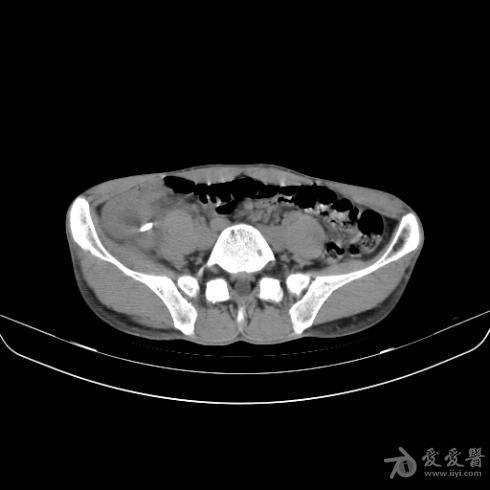

阑尾炎(粪石)ct

图片尺寸2981x1677